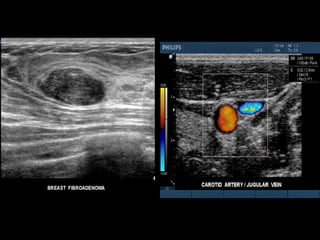

ULTRASONOGRAFIA

* 3 to 1 MHz extended operating frequency range  *2D, Live 3D Echo, Color Doppler with 2D, biplane  and 3D  Adult and pediatric cardiology applications     *10 to 5 MHz extended frequency range  *Biplane (transverse and sagittal) Steerable pulsed Doppler,  Color Doppler, and imaging Endocavitary applications  including urology, endorectal and endovaginal  *Supports transrectal biopsy procedures

* 3 to1 MHz extended operating frequency range *2D, Live 3D Echo, Color Doppler with 2D, biplane and 3D  Adult and pediatric cardiology applications   *10 to 5 MHz extended frequency range *Biplane (transverse and sagittal) Steerable pulsed Doppler, Color Doppler, and imaging Endocavitary applications including urology, endorectal and endovaginal *Supports transrectal biopsy procedures